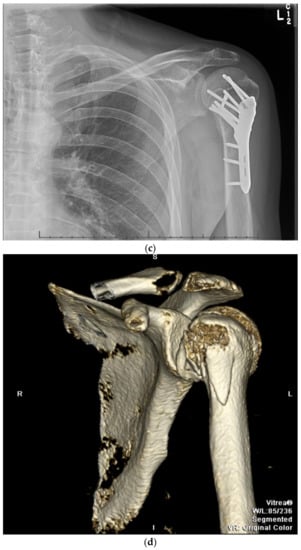

9. Open Reduction and Internal Fixation

11. Open Reduction Internal Fixation with an Intramedullary Nail